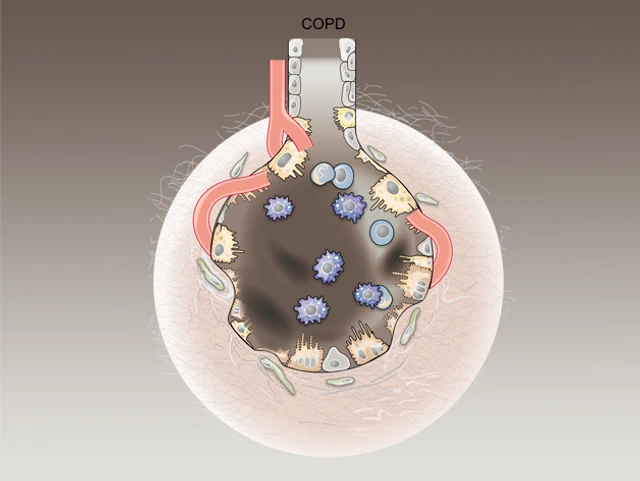

Many environmentally triggered lung diseases are still considered incurable. We explore the immunological mechanisms underlying chronic lung diseases such as COPD, lung fibrosis, asthma, lung cancer and the complications following lung transplantation. We want to translate our findings into preventative and therapeutic approaches for patients.

Many environmentally triggered lung diseases are still considered incurable. We at the Institute of Lung Health and Immunity (LHI) explore the immunological mechanisms underlying chronic lung diseases such as COPD, lung fibrosis, asthma, lung cancer and the complications following lung transplantation. We want to translate our findings into preventative and therapeutic approaches for patients.